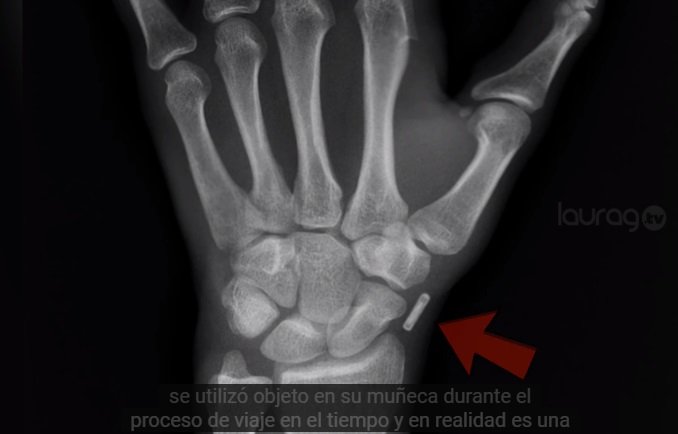

Ya que arriesgó su vida para viajar a nuestra época, ante escépticos, aseguró tener evidencia sólida que respalda sus predicciones. Al final del vídeo explican que se sometió a una prueba de RX y se detectó un objeto en su muñeca que le permitió el viaje en el tiempo.